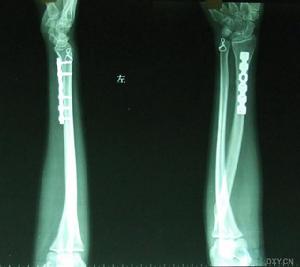

橈骨下端骨折 本病的輔助檢查主要是X線檢查,X片可清楚顯示骨折及其類型。伸直型者橈骨骨折下端向背橈側移位,關節面掌側及尺側傾斜角度變小、消失、甚至反向傾斜。橈骨遠骨折端與近側相嵌插,有的合併尺骨莖突骨折及下尺橈關節分離。屈曲型骨折橈骨下端向掌側移位。對輕微外力致傷的老年患者,應作骨密度檢查,以了解骨折疏鬆情況。

X片可清楚顯示骨折及其類型。伸直型者橈骨骨折下端向背橈側移位,關節面掌側及尺側傾斜角度變小、消失、甚至反向傾斜。橈骨遠骨折端與近側相嵌插,有的合併尺骨莖突骨折及下尺橈關節分離。屈曲型骨折橈骨下端向掌側移位。對輕微外力致傷的老年患者,應作骨密度檢查,以了解骨折疏鬆情況。

5、粉碎性骨折復位困難或復位後不易維持者(如巴爾通骨折),常需手術復位,克氏針、螺絲釘或T型鋼板內固定。術後石膏固定6周。